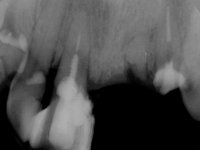

Paciente do sexo masculino, com 64 anos de idade, não fumador, recorreu á minha consulta após traumatismo do sector anterior. Os dentes 2.1 e 2.2 apresentavam extensas fraturas infra ósseas. Os dentes 1.2 e 1.1 apresentavam-se ferulizados com uma resina composta na zona inter-proximal. O dente 1.1 apresentava um tratamento endodôntico sofrível e um poste intra-radicular. O dente 1.2 estava vital e tinha uma extensa restauração da resina composta. Estando ferulizados, não foi possível avaliar o grau de mobilidade dentária de cada um dos dentes, mas o conjunto não tinha mobilidade. Após exame clínico e Imagiológico conclui-se que as raízes dos dentes 2.1 e 2.2 tinham extração indicada. O paciente estava reabilitado provisoriamente com uma prótese removível esquelética com 3 dentes. Apresentava algum comprometimento periodontal e os dentes mostravam as superfícies oclusais e incisais desgastadas. Higiene oral razoável.

Foi proposta a extração das raízes dos dentes 2.1 e 2.2. e colocação de 1 implante no local do dente 2.1 que suportaria uma ponte aparafusada com 2 elementos. O dente 2.1 sobre o implante e o 2.2 em extensão. Se em termos periodontais a zona do 1.2 e 1.1 continua-se a maturar sem problemas e se garantir-se um bom suporte sem mobilidade, seria proposto refazer o tratamento endodôntico do 1.1 e fazer o tratamento endodôntico no 1.2. Posteriormente e após colocação de postes intra-radiculares os dentes seriam reabilitados com uma ponte com 2 elementos. Após a colocação da ponte de2 elementos sobre o implante colocado no local do 2.1, o paciente sofre um novo traumatismo que compromete a viabilidade dos dentes 1.2 e 1.1. Nessa altura é proposta a colocação de um novo implante no local do dente 1.1 e confeção de uma ponte de 4 elementos com os dentes 1.1 e 2.1 sobre os implantes e os dentes 1.2 e 2.2 como pônticos em extensão.

6 meses após a colocação da ponte, o paciente sofre um novo traumatismo comprometendo a viabilidade dos dentes 1.2 e 1.1. Foi realizada uma prótese removível acrílica para reabilitar provisoriamente o paciente enquanto foram extraídos os dentes 1.2 e 1.1 e foi colocado o implante no local do dente 1.1. Passados 3 meses foi realizada uma impressão ao implante colocado no 1.1 e simultaneamente foi feito um arrasto da ponte dos dentes 2.1 e 2.2. Para esse efeito no implante 2.1 foi utilizado um parafuso de uma peça de transferência. Dessa forma conseguiu-se impressionar corretamente a arquitetura gengival do sector antero-superior. O objetivo era simultaneamente impressionar corretamente esta zona e aproveitar a estrutura metálica desta ponte para confecionar a nova ponte de 4 elementos. Foi colocado um parafuso de cicatrização no implante 2.1 e foram acrescentados os dentes 2.1 e 2.2 na prótese removível. Com perícia laboratorial foi criada uma nova infraestrutura metálica de 4 elementos assente nos implantes 1.1 e 2.1 e com os elementos pônticos suspensos 1.2 e 2.2. No implante 2.1 manteve-se a conexão interna ao implante no implante 1.1 optou-se por uma peça intermédia facilitando a inserção da infraestrutura. A nova infraestrutura foi verificada em boca. Como pode ter havido alguma alteração da arquitetura gengival com a remoção da ponte e colocação do parafuso de cicatrização no 2.1, foi feita uma chave de silicone para permitir uma impressão de arrasto da infraestrutura metálica. Uma nova gengiva artificial foi realizada no modelo de trabalho de acordo com esta impressão de arrasto. Foi colocada cerâmica de tonalidade coronária e gengival. A peça protética foi aparafusada lentamente em boca para permitir uma adaptação dos tecidos moles. Após o correto assentamento e verificação imagiológica a ponte foi definitivamente apertada em boca e os orifícios de acesso obturados. Independentemente dos infortúnios que o paciente teve, pude ter a satisfação de o ver contente com esta reabilitação.